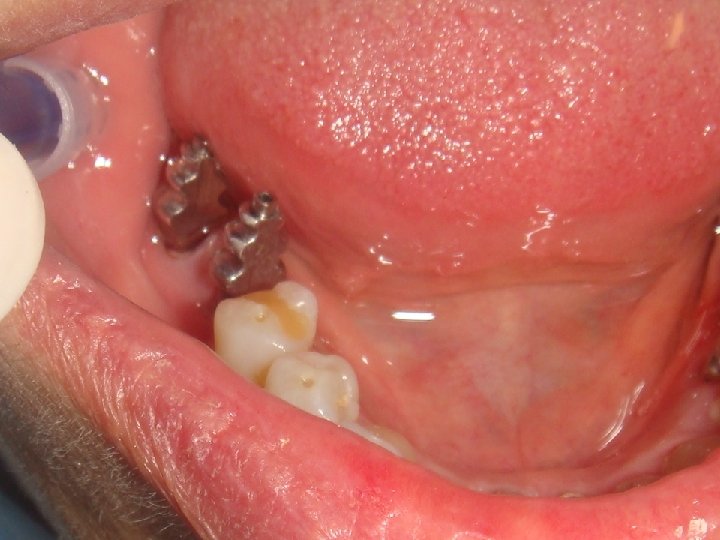

Abstract No. 2: (cont. . ) Planning implant Prosthodontics is mainly related to the available amount of residual bone and the load capacity of an implant. Especially the bone anchorage and the component strength of an implant limit the construction design of a suprastructure. Therefore to gain a deep insight into biomechanics is a prerequisite for an adequate planning of an appropriate construction design. In case of very high load capacity of an implant the expanded treatment possibilities are: • unsplinted single posterior crowns • physiological occlusal surface • long cantilevers • inclusion of patients with excessive bruxism • short implants • small implant diameter

Abstract No. 2: (cont. . ) The important consequence in the daily work of the last two items - the ability to use short and small implants due to an excellent bone anchorage - is a reduced need of augmentation procedure resulting in a huge increase of patients which accept implant based therapies only with minimal invasive medical intervention. However, an aesthetic result borne on a small implant-diameter requires a creative implementation on the part of the dental technician, taking the surrounding soft tissues (emergence profile) into due account. The submucosal shape of the abutments or the crown should correspond to a natural tooth and should be designed like an ovate-pontic of a bridge.